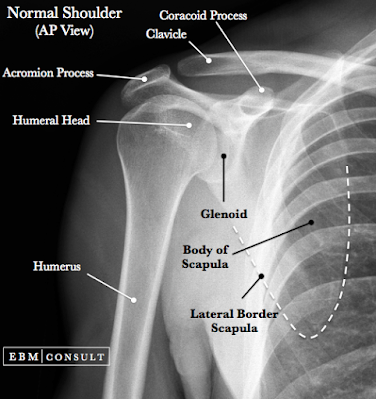

That dang Acromion Process when it flaires it causes severe pain that wakes you from a deep sleep and I have found no pain killer that even touches it.  I mean hydro condone?  does not touch it and I seldom take real pain drugs. Mostly cause they make me pukey.  And pukey on top of pain not my favorite thing. The last time I had problems with this I actually had to sleep sitting up at a table with my head on a pillow.  I have been up the last two nights, woke out of a deep sleep with this...